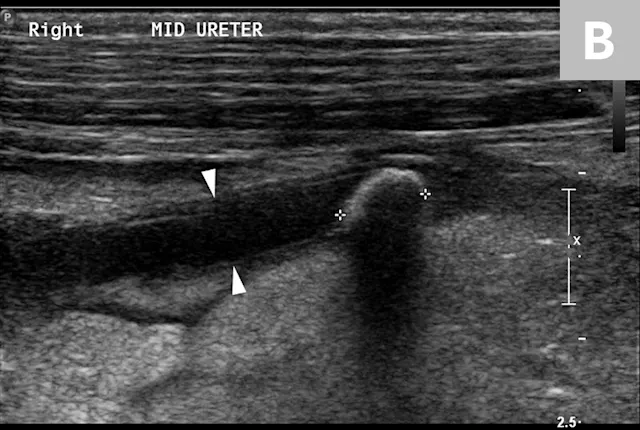

Ureteral calculi are a common cause of ureteral obstruction; localization of ureteral calculi is imperative prior to choosing appropriate management. While ureteral calculi have been reported as the most common cause of ureteral obstructions, other causes such as iatrogenic ligation, blood clots, tumor, strictures (congenital and acquired), solidified blood stones, and a circumcaval ureter have been reported.4-7

The obstruction can be located at any point of the ureter and can vary in severity. Normal ureters are typically not seen on ultrasonography due to their small size. The easiest way to locate a dilated ureter is to trace the ureter from the renal pelvis. In most cases, the ureter is dilated proximal to the site of an obstruction and tapers to a more normal appearance distal to the site of obstruction. Imaging can also reveal retroperitoneal effusion which can result from ureteritis and possible urine leakage.

Clinical signs associated with ureteral calculi may range from chronic non-specific signs to acute or chronic renal failure. The presence of hydronephrosis can be highly suggestive of a ureteral obstruction (Figure 6).

FIGURE 6A

Mild to moderate right hydronephrosis and proximal ureteral dilation in a Dalmatian.